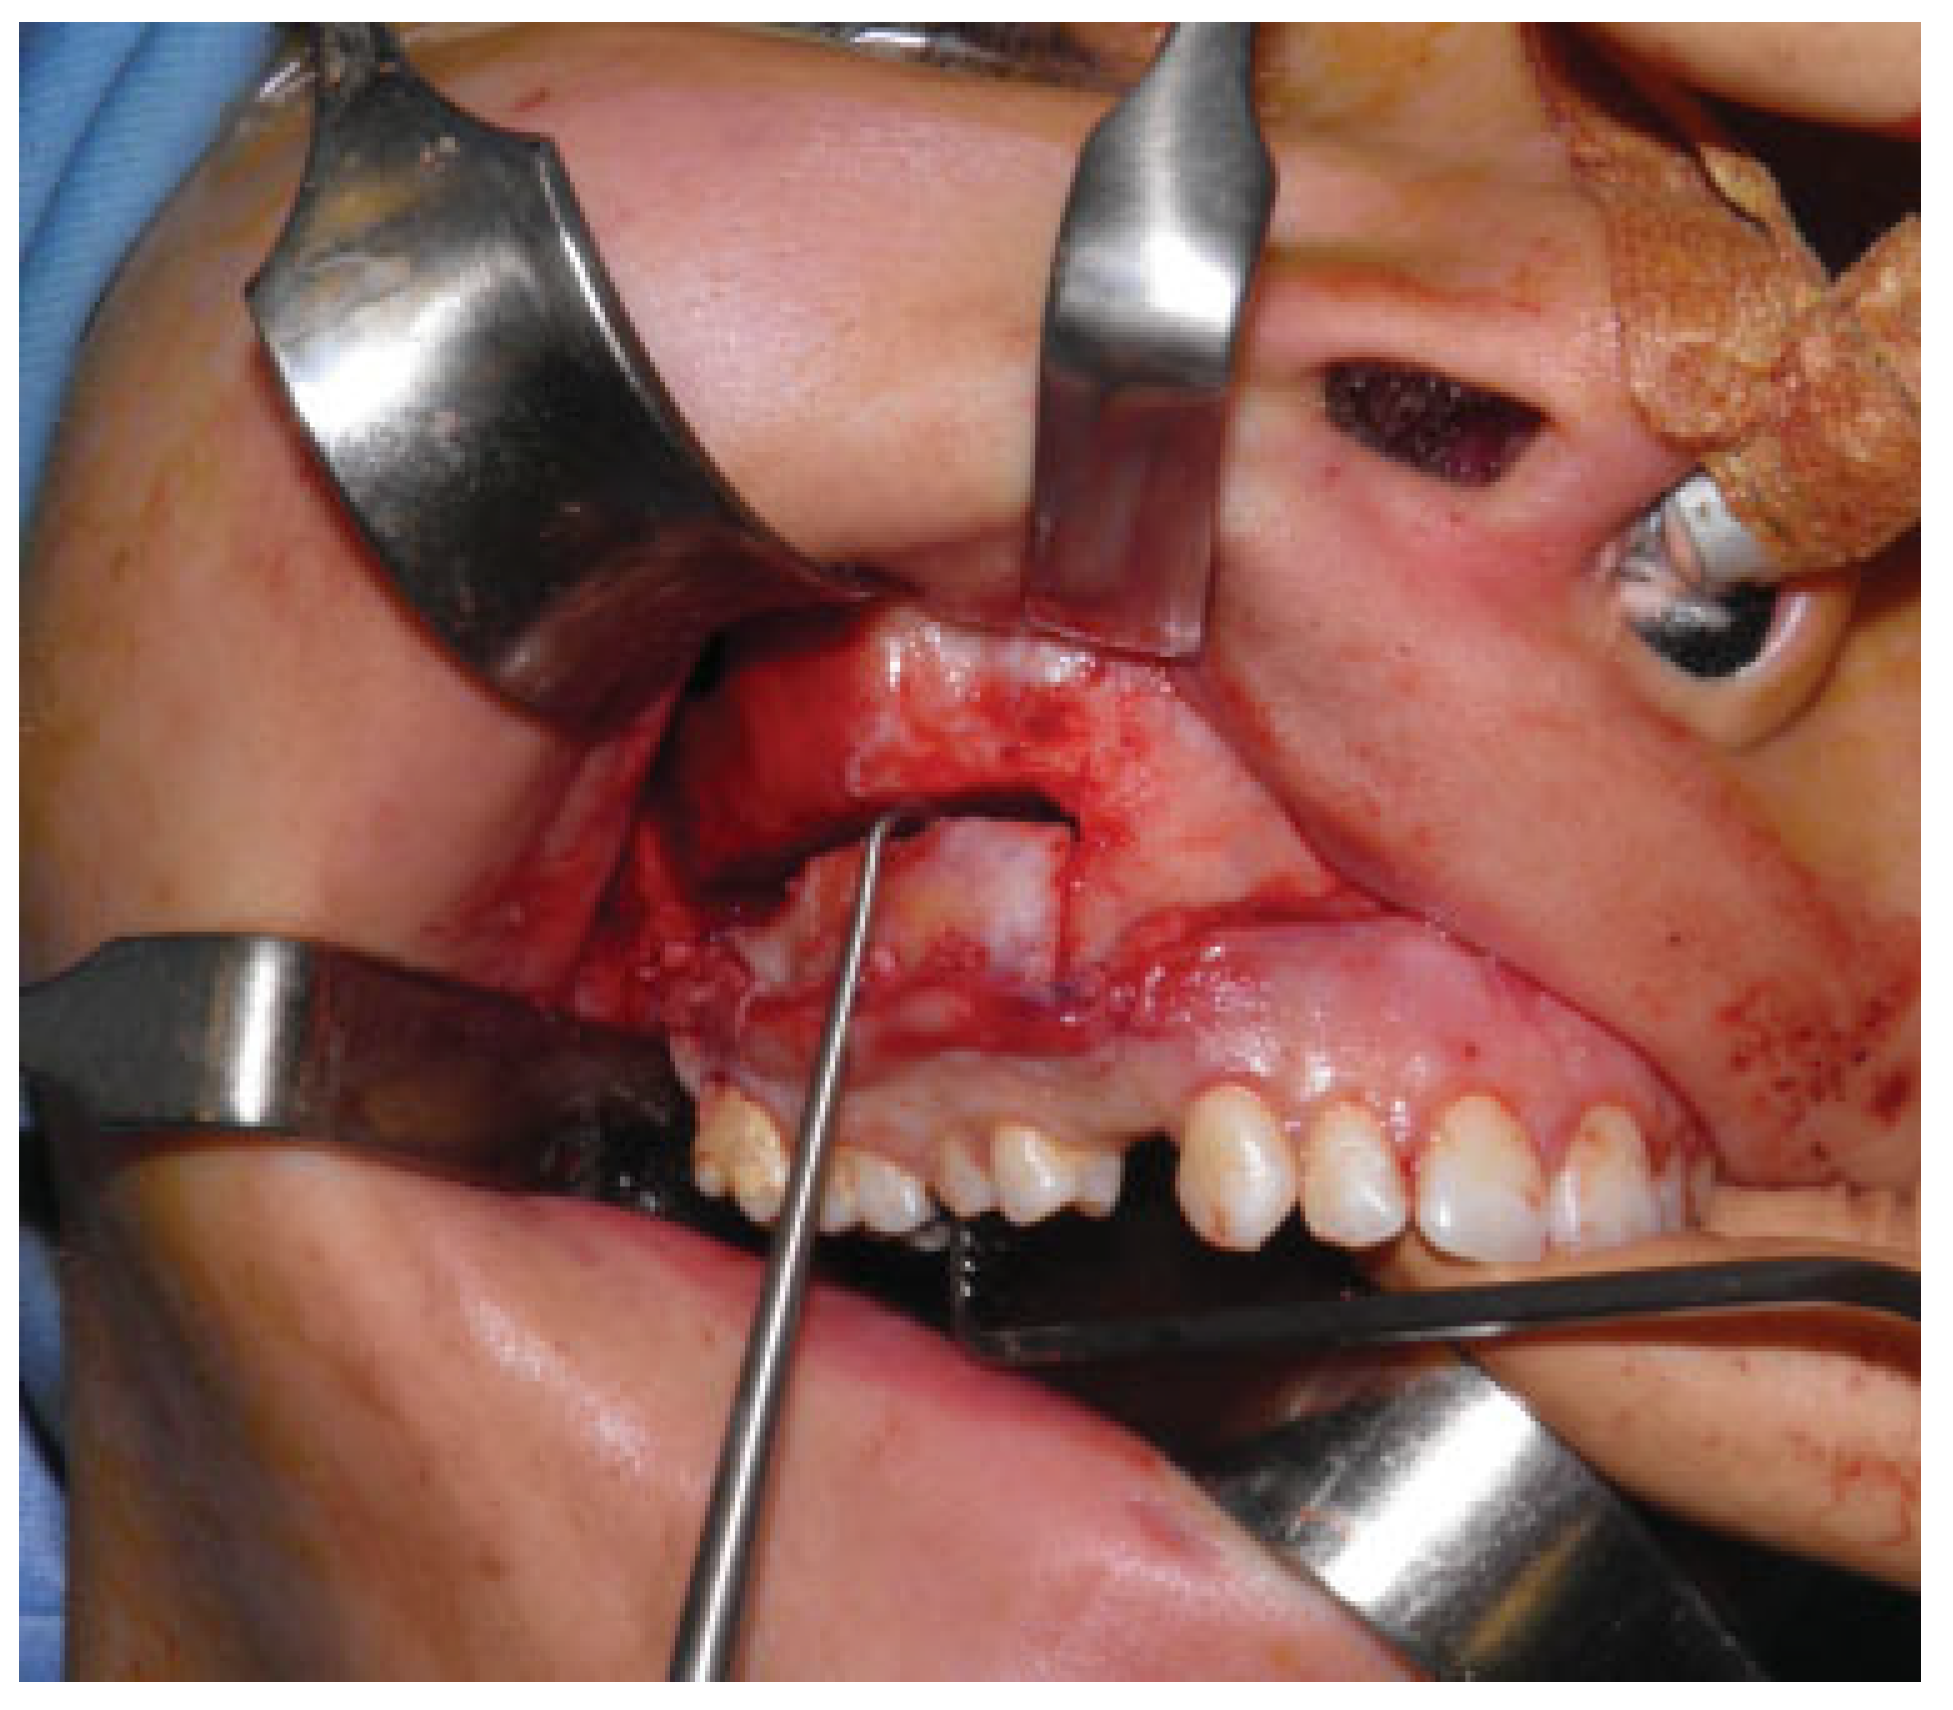

The main surgical steps were infiltration, incision of the top right maxillary mucosa, bone exposure, and preparation of a vestibular mucoperiosteal flap. Thereafter right zygomatic bone and upper maxilla shaving and simmetrization with the contralateral side were completed (Figure 2).

Figure 2. Remodeling and shaving of the upper maxilla and zygoma.